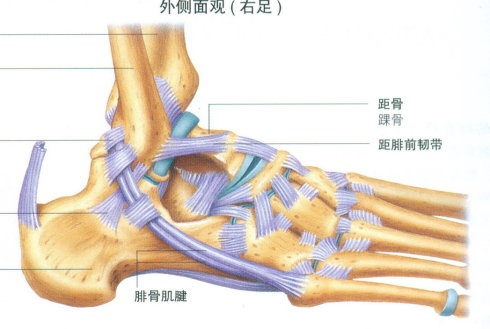

踝关节由胫腓骨下端与距骨组成。其骨折、脱位是骨科常见的损伤,多由间接暴力引起踝部扭伤后发生。根据暴力方向、大小及受伤时足的位置的不同可引起各种不同类型的骨折。目前临床常用分类方法是Lange-Hansen分类法、Davis-Weber分类法和AO分类法。Lange-Hansen分类法于1950年提出,根据足在受伤时的位置和暴力的方向将骨折分为旋后/内收型、旋后/外旋型、旋前/外展型和旋前/外旋型四类,每一类又根据骨折程度及是否伴有韧带软组织损伤而分为不同的亚类。该分类对于踝关节不稳定骨折的闭合复位有指导意义。Davis-Weber分类法根据外踝骨折的位置,把踝关节骨折分为A、B、C三型,该分类以下胫腓联合为界将骨折分为下胫腓联合水平以下的损伤(A型)、经下胫腓联合的腓骨骨折(B型)以及下胫腓联合以上损伤(C型),较简单,使用方便,但却不能说明整个踝关节各种复杂改变。国际创伤学会(AO)进一步细化了Davis-Weber分类法,提出了AO分类法。